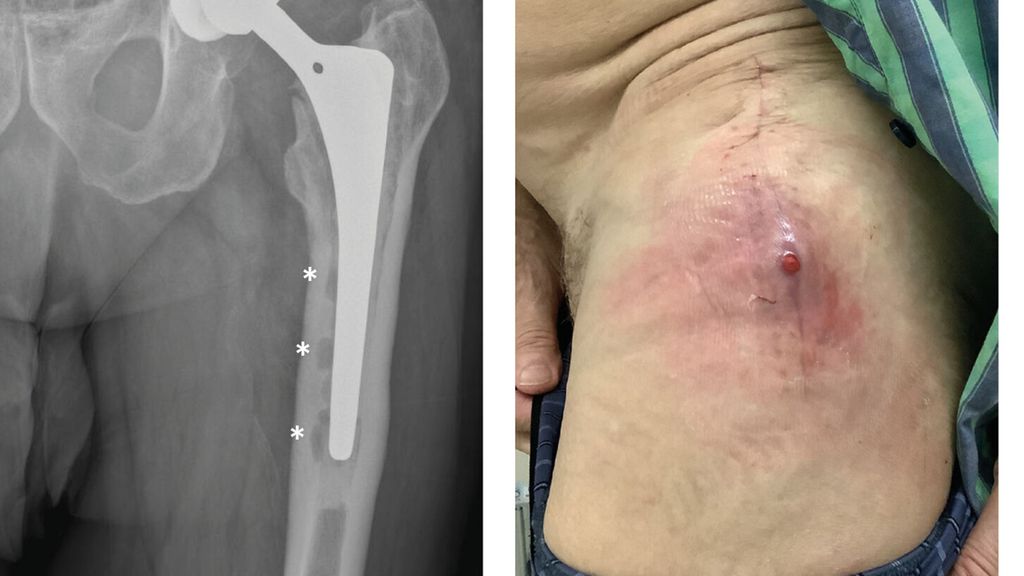

Anhand der klinischen Zeichen und der Symptomdauer unterscheidet man zwischen akuter und chronischer PPI. Die akute PPI ist durch eine kurze Symptomdauer (<3 Wochen) charakterisiert. Sie tritt entweder in der frühen (<4 Wochen) Phase nach endoprothetischem Gelenkersatz (akute postoperative PPI) oder aber verzögert (>4 Wochen, ggf. erst mehrere Jahre) nach Endoprothesenimplantation im Rahmen einer hämatogenen Streuung eines endoprothesenfernen Infektionsherdes (akute hämatogene PPI) auf. Typischerweise imponieren hier lokale Infektionszeichen wie Schmerzen, Schwellung, Rötung, Überwärmung oder eine prolongierte Wundsekretion (>7 Tage). Die Unterscheidung zwischen akuter und chronischer PPI basiert auf den Eigenschaften des bakteriellen Biofilms. Beim Vorliegen einer akuten PPI ist von einem unreifen bakteriellen Biofilm auf der Endoprothesenoberfläche auszugehen. Bei der chronischen PPI (>4 Wochen postoperativ) mit längerer Symptomdauer (>3 Wochen) liegt hingegen ein potenziell reifer Biofilm vor. Die klinischen Symptome sind in der Regel weniger ausgeprägt. Jedoch kann das Vorliegen einer kutanen Fistel oder von radiologischen Zeichen der Endoprothesenlockerung auf eine chronische Infektion hinweisen (z. B. Abb. 1).

Abb. 1: Patient mit chronischer Hüftendoprotheseninfektion. Radiologisch zeigen sich infektionsbedingte periprothetische Osteolysen (*, a) und klinisch imponiert eine kutane Fistel (b).